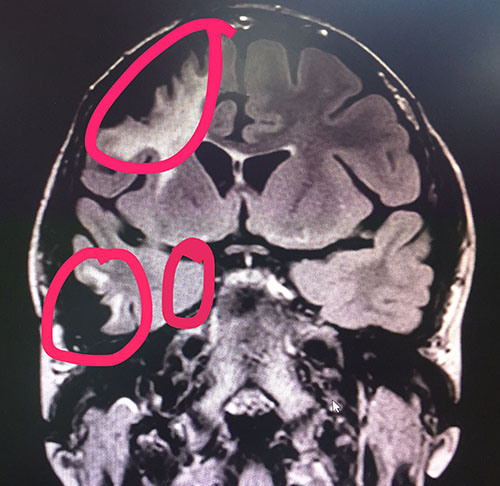

▲標(biāo)記處為需要進(jìn)行手術(shù)的癲癇病灶區(qū)

1、左側(cè)海馬信號(hào)增高,體積稍變小,考慮海馬硬化可能,結(jié)合臨床。2、MRS 雙側(cè)海馬Cho峰稍微升高(右側(cè)NAA/Cr+Cho=0.49;左側(cè)NAA/Cr+Cho=0、54)結(jié)合臨床。3、右側(cè)額葉及顳葉軟化灶形成,結(jié)合臨床病史。

楊忠旭博士親自為李雪做了手術(shù),但因其有二十多年的癲癇史,又曾在其他醫(yī)院進(jìn)行過(guò)“顱內(nèi)電極置入術(shù)和右側(cè)額葉致病灶切除術(shù)”手術(shù),她大腦部分正常結(jié)構(gòu)已經(jīng)發(fā)生了改變,有三處癲癇病灶區(qū)(右側(cè)額極蛛網(wǎng)膜囊腫癲癇病灶區(qū)、右側(cè)顳葉癲癇病灶區(qū)、右側(cè)海馬癲癇病灶區(qū))需要進(jìn)行手術(shù),如果再次進(jìn)行手術(shù),就必須小心、小心、再小心,這就為這次手術(shù)的進(jìn)行增加了難度。